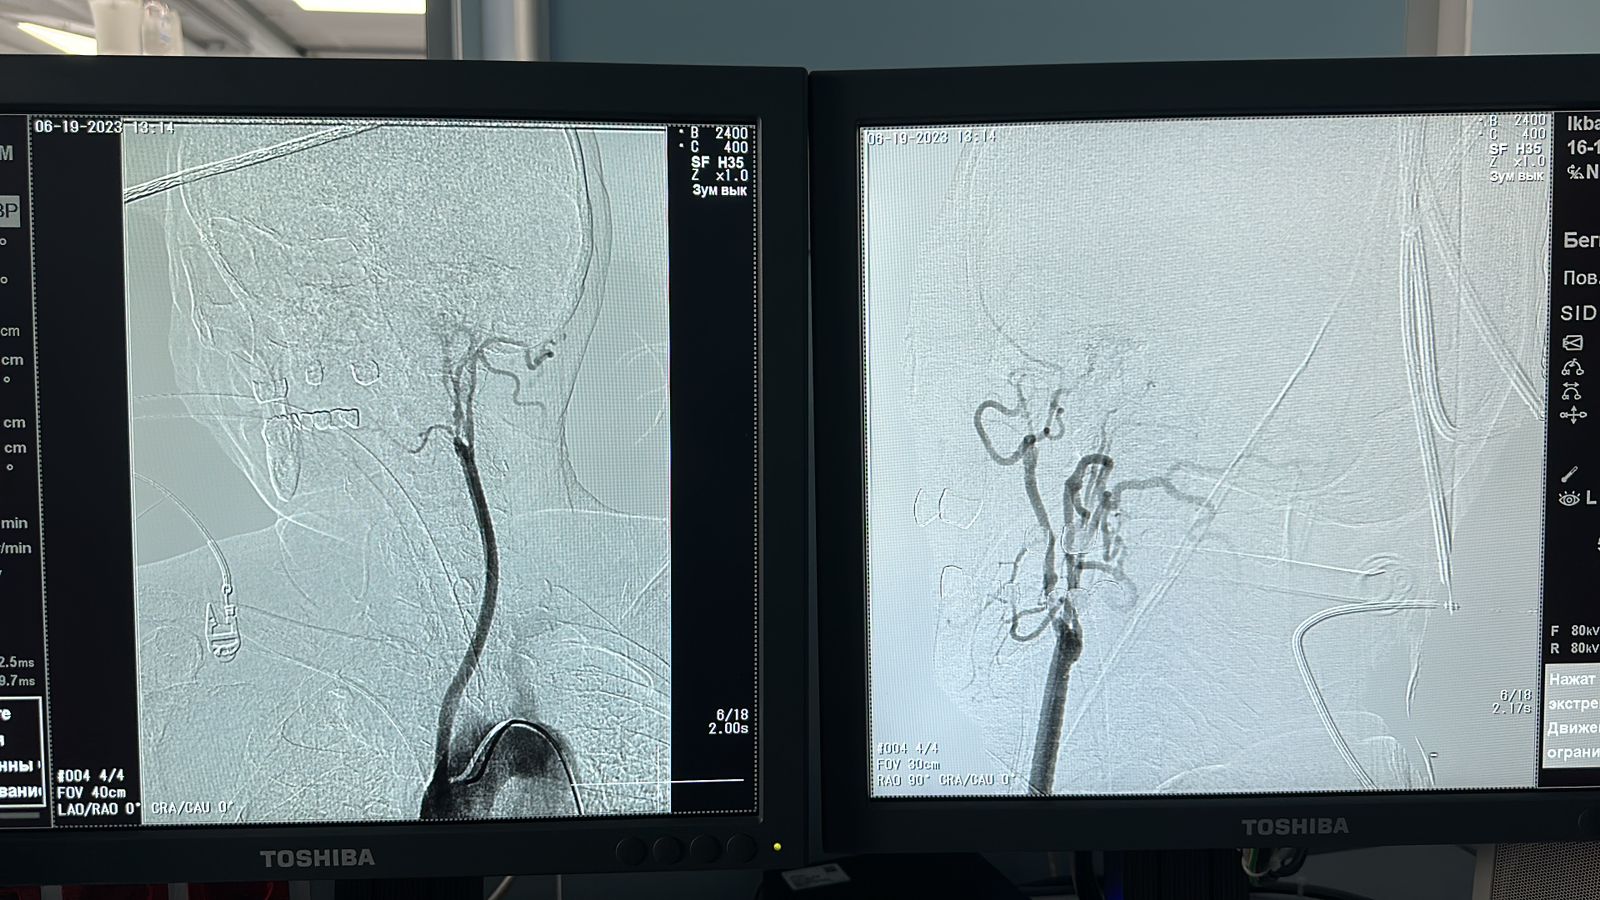

– بىزگە كەلگەن ناۋقاستىڭ ميعا باراتىن ەڭ نەگىزگى ەكى جاقتى ىشكى ۇيقى ارتەريالارى, سونىمەن قوسا ومىرتقالىق ارتەريالارى تولىق بىتەلىپ قالعان بولاتىن. باستاعى قانتامىرلار بۇعانا ارتەرياسىنان شىعاتىن مويىندىق بايلام تامىرىنان قورەكتەنىپ جۇرگەن. بۇل جەردە كارديوحيرۋگتەردىڭ دە ارالاسۋى قاجەت ەدى. سەبەبى جۇرەكتەن شىعاتىن اورتا تامىرىنا بلوگ ورناتۋ جوسپارلاندى. شەتەلدىك ارىپتەستەردىڭ تاجىريبەسىن زەرتتەي كەلە جانە وزىمىزدەگى زاماناۋي تەحنيكالىق مۇمكىندىكتى پايدالانا وتىرىپ كارديوحيرۋرگيا بولىمشەسىنىڭ مەڭگەرۋشىسى الىبەك تويباەۆپەن بىرلەسە العاش رەت «تاكاياسۋ» دياگنوزىنا وپەراتسيا جاساپ شىقتىق. «كەلىسىپ پىشكەن تون كەلتە بولماس» دەگەندەي, قازىر ناۋقاستىڭ جاعدايى جاقسى, باستاعى اۋىرسىنۋلار تارقاعان, – دەيدى نەيروحيرۋرگ دارىگەر يسلامبەك مۇسابەكوۆ.